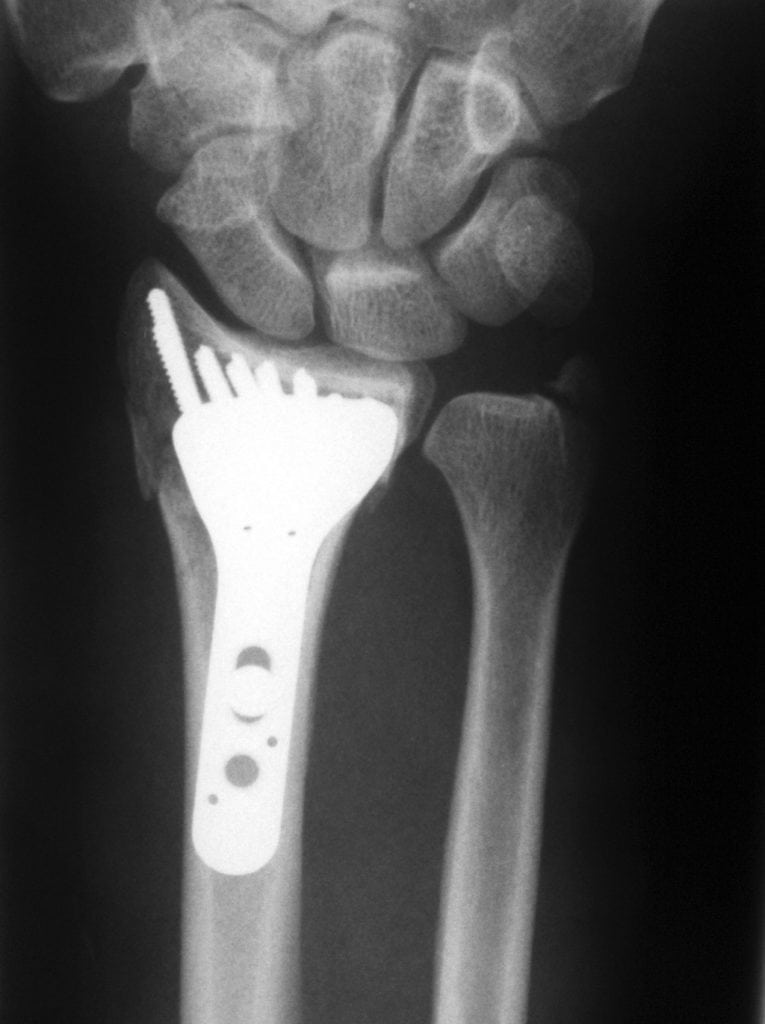

После подтверждения диагноза врачи определяются с лечебной тактикой. Чаще всего они выполняют закрытое вправление с дальнейшей фиксацией кисти гипсовой лонгетой. Спустя 4 недели гипс снимают и оценивают состояние лучезапястного сустава. При наличии нестабильности хирурги выполняют фиксацию спицами Киршнера.

Если врачам не удается выполнить вправление закрытым способом, они используют компрессионно-дистракционный аппарат Илизарова. При осложненных вывихах медики проводят хирургическое лечение вывихов кисти руки. В случае повреждения срединного нерва операцию делают без промедлений.